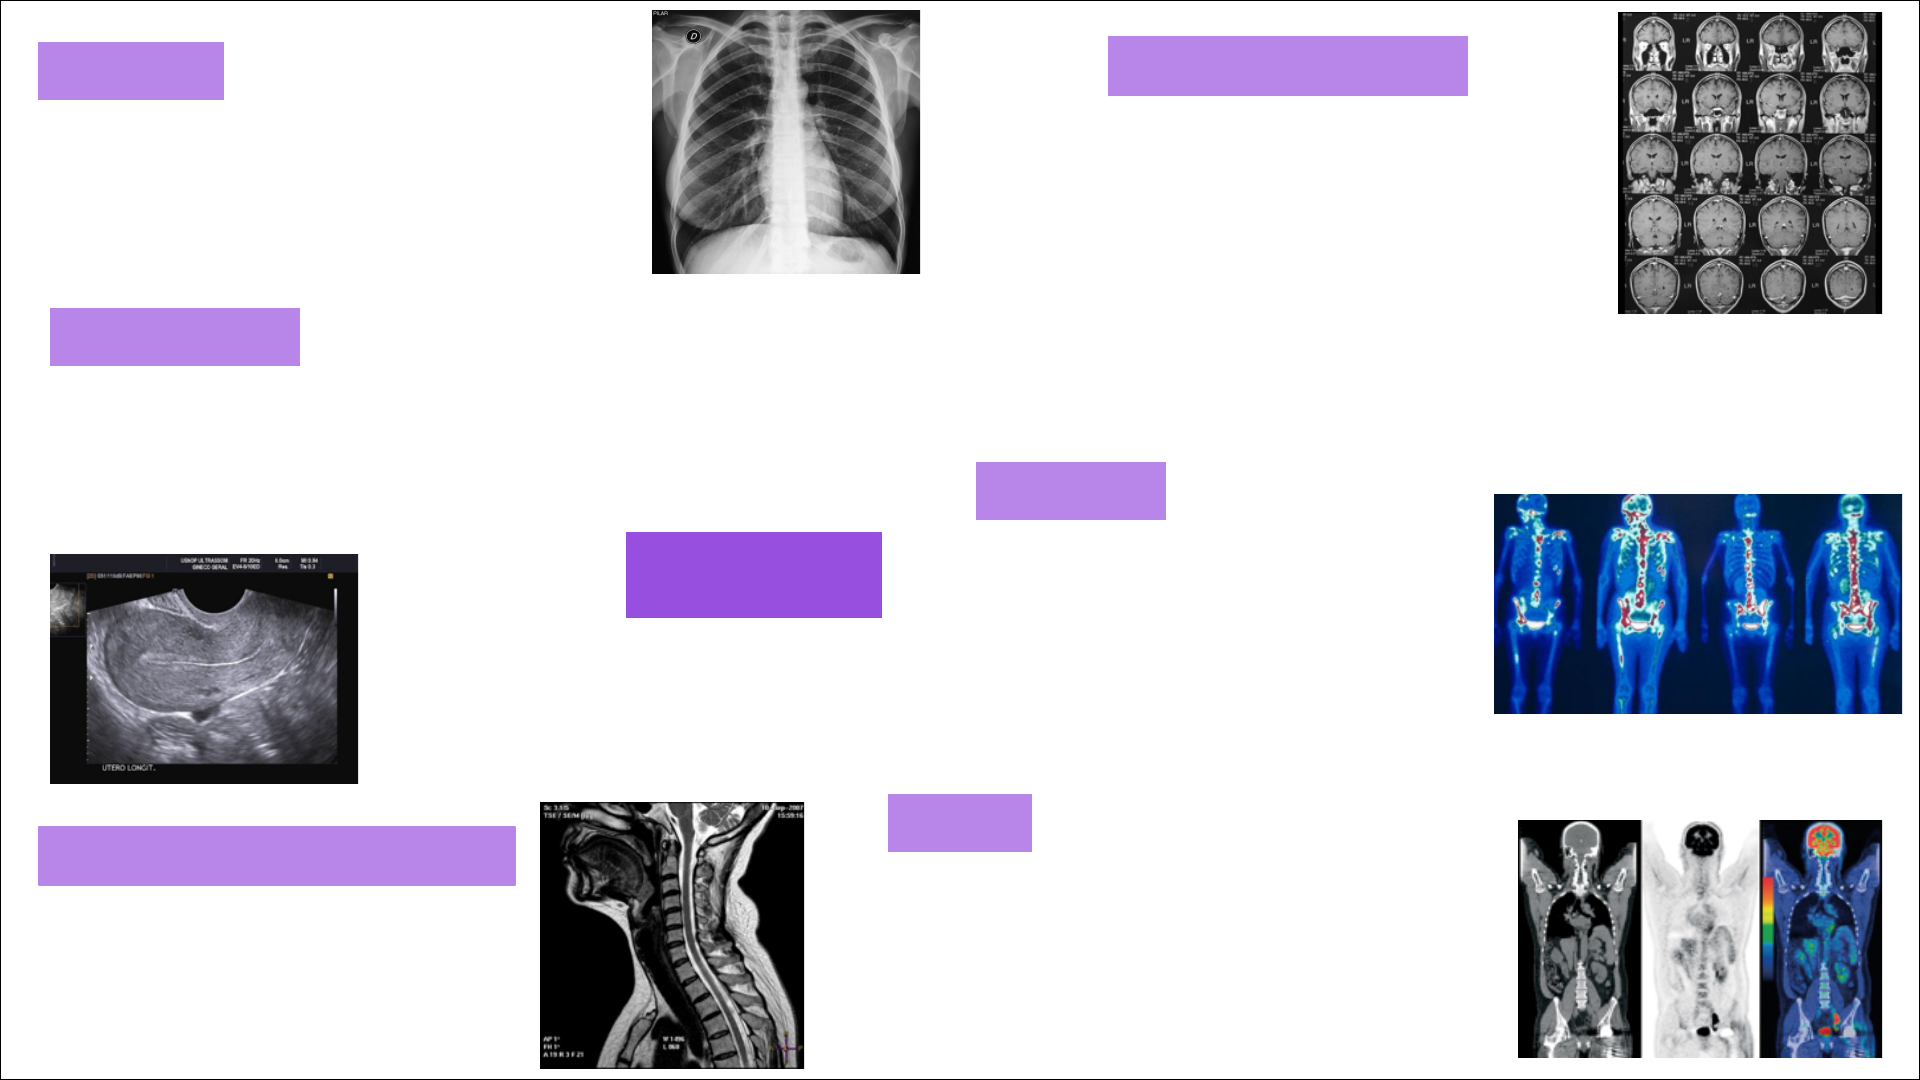

Bioimagem

Radiografia Ressonância Magnética

Tomografia Computadorizada

Cintilografia

Ultrassonografia

PET-CT

1. Utiliza radiação ionizante

2. Ossos e órgãos como objeto de análise

3. Tem maior foco na anatomia

2. Órgãos como objeto de análise

1. Não utiliza radiação ionizante

3. Tem maior foco na fisiologia